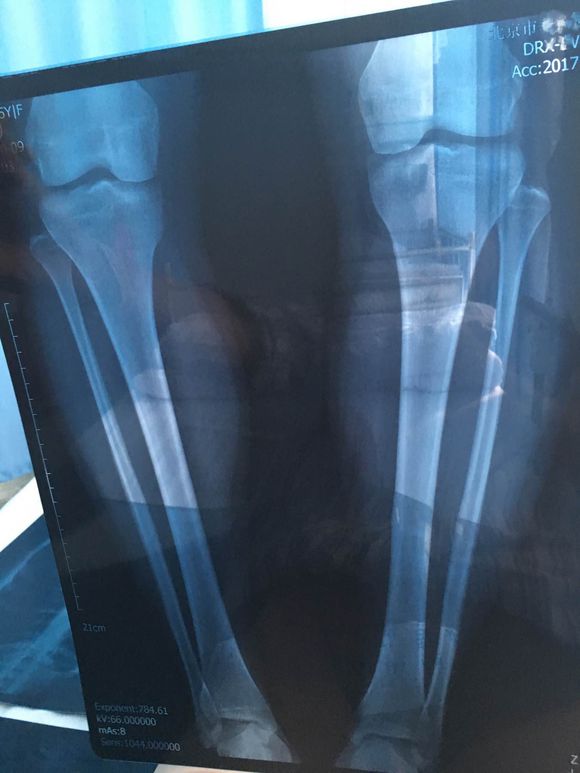

地方还是比较好找的,之前说好准备的X光片什么的我也都提前弄好了,去了医生看过之后做了详细的分析,说我这种情况除了膝内翻还有骨盆前倾的症状而且还比较严重,解释了一下治疗方法时候便开始进行治疗;进治疗室那一刻其实我还是蛮害怕的,医生和护士都在安抚我的情绪,让我不要紧张,打了麻药之后我脸就转过去了,害怕不敢看,整个手术持续了十几分钟,中间有微微的痛感,在护士的搀扶下我自己回到休息室等待麻药劲儿过去,之后进行力量训练,姿势训练,来恢复我不平衡的软组织。